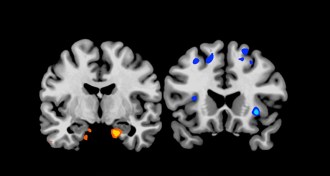

Brain stimulation restores movement in rats with spinal cord damage

Implanted electrodes might help paralyzed humans walk.